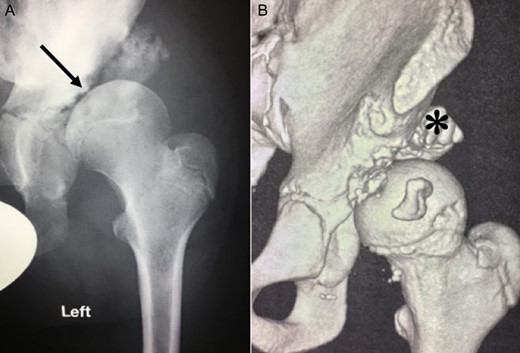

Ten years ago, a 12-year-old male presented to our clinic complaining about limping and massive swelling of the left hip. Figure 1 shows the initial X-ray and the 3D reconstruction of the left hip at first presentation when the femoral head, had already destroyed the lateral edge of the acetabulum like a mortar. Severe pain episodes have apparently not been noticed and a former hip dysplasia was not known. A brief clinical history revealed that the patient presented repeated episodes of finger biting and fevers from 2 to 8 years old. The intelligence level of the patient was at an average. The patient was admitted to a paediatric neurologist and a genetic test. A mutation of the NTRK1 gene was found and the diagnosis of CIPA was established. The right hip initially appeared to be normal and the patient was walking, therefore surgical reconstruction for the left hip was proposed due to massive swelling, inability of normal walking and significant limb length discrepancy. A Tönnis/Kalchschmidt triple pelvic osteotomy with open reduction and a shortening varus derotation osteotomy (VDRO) of the femur was performed (Fig. 2A–B). After 3 months the patient was walking again but another 3 months later the hip dislocated again without severe pain. Although the femoral head was already damaged the hip joint was reconstructed again by open reduction, capsular reconstruction with suture anchors and a trevira tube and a movable external fixator was used to temporary stabilize the joint (Fig. 3). The right hip at this time was still intact and was protected with a pneumatic orthotic device. A few months later in 2009, despite all surgeries, the left hip had entirely lost congruency and the right hip developed subluxation despite conservative treatment (Fig. 4). The patient was still walking so the decision to reconstruct the right hip with open reduction, capsular augmentation with a trevira tube, a triple pelvic osteotomy and VDRO was made (Fig. 5). Few months later this reconstruction failed as well and the hip dislocated without severe pain (Fig. 6).

(A + B): (2008) (A) X-ray of the left hip demonstrating subluxation of the femoral head which is destroying the edge of the acetabulum (arrow) like a mortar. (B) 3-D reconstruction of the hip showing bony debris of the acetabulum edge forming a secondary acetabulum (asterisk) trying to cover the femoral head.